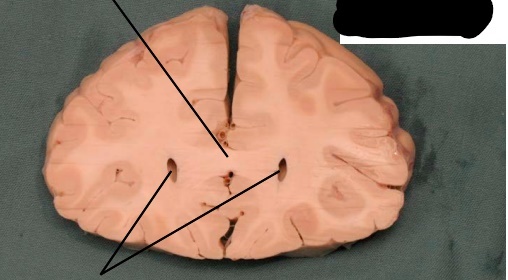

how can the lateral ventricles localize relative position in the brain?

label, note important features